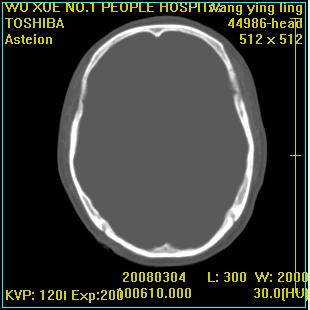

标题: CT12023:女,50岁,头部包块二月,伴轻微头痛,不伴发热。 [打印本页]

标题: CT12023:女,50岁,头部包块二月,伴轻微头痛,不伴发热。

这种病例还是比较多见,起源于颅骨板障,向颅内和颅外生长,考虑血管瘤或嗜酸性肉芽肿,要是有增强ct就好了。

多发溶骨性破坏,骨嗜酸性肉芽肿可能,转移瘤待排除,建议进一步检查。